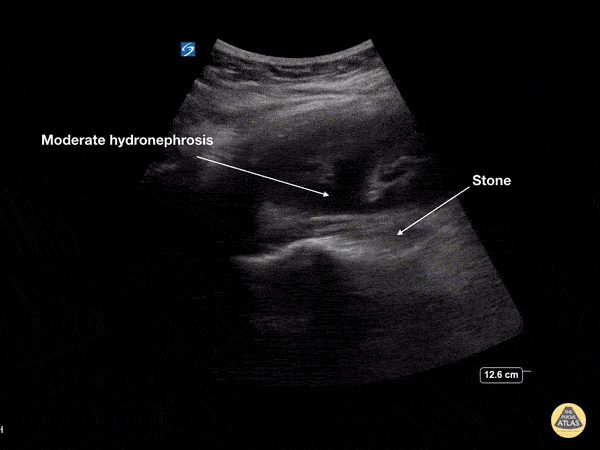

Renal/GU - Moderate Hydronephrosis

This young female presented with colicky left flank pain worsening over the previous 24 hours. POCUS showed moderate hydronephrosis with rounding of the calyces of the left kidney collecting system. The stone is seen at the ureteropelvic junction (UPJ) as a hyperechoic structure with posterior acoustic shadowing measuring 7mm on CT. At ureteroscopy, the stone was retrieved, fragmented and a double J stent was placed Dr Cian McDermott, Mater University Hospital, Dublin, Ireland